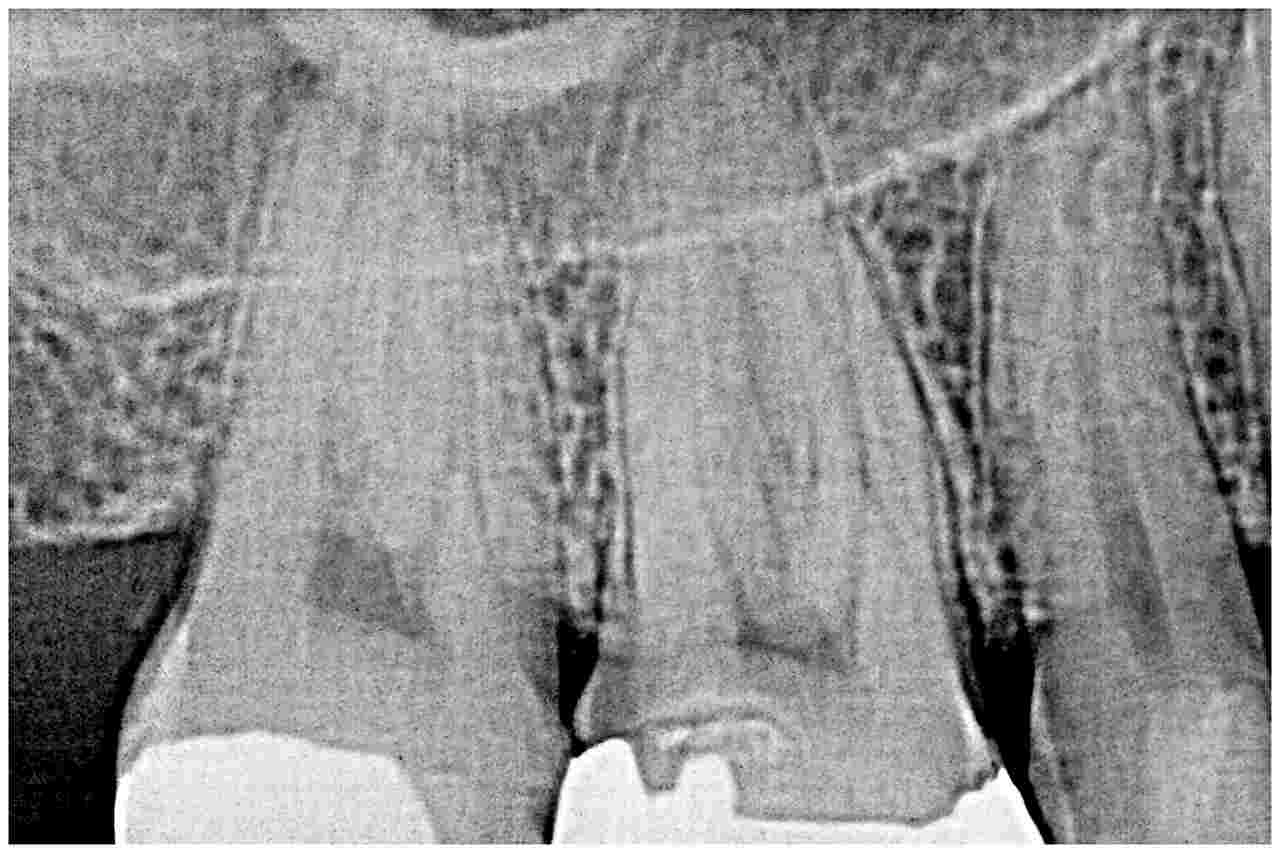

セレックプライムスキャンを用いたセラミック治療の実際 良いものを安価に|お知らせ |広島市安佐南区の歯科医院 セレックプライムスキャンを用いたセラミック治療の実際 良いものを安価に トップ お知らせ・ブログ お知らせ セレックプライムスキャンを用いたセラミック治療の実際 良いものを安価に セレックプライムスキャンを用いたセラミック治療の実際 良いものを安価に かなり大きめのインレーが入っています 咬合面をほぼ覆う大きな被せが入っています レントゲンで虫歯の大きさを把握していきます 銀歯をはずした直後になります 虫歯を神経に気を付けながら慎重に除去していきます CR樹脂にて覆罩して型取りを行いセレックセラミックを作成していきます このように本来の歯のようにきれいに仕上がりました 喜んでいただきました Web診療予約 初めての方へ 選ばれ続ける理由 院内設備について 歯が痛いしみる一般歯科 歯がぐらぐらする歯周病 健康な歯を保ちたい予防歯科 子供の虫歯予防をしたい小児歯科 銀歯をセラミックに審美歯科 白い歯を目指しませんか?ホワイトニング 矯正専門医がいるので安心矯正歯科 抜けた歯を補いたいインプラント・入れ歯 医院案内 スタッフ紹介 メリィハウス歯科クリニックオフィシャルホームページ ラベンダー歯科クリニックオフィシャルホームページ お知らせ・ブログ ホーム 診療科目 一般歯科 歯周病治療 予防治療 小児歯科 審美治療 ホワイトニング 矯正歯科 入れ歯・インプラント マウスピース矯正 初めての方へ 院長・スタッフ 設備紹介 医院案内・アクセス メニューを閉じる